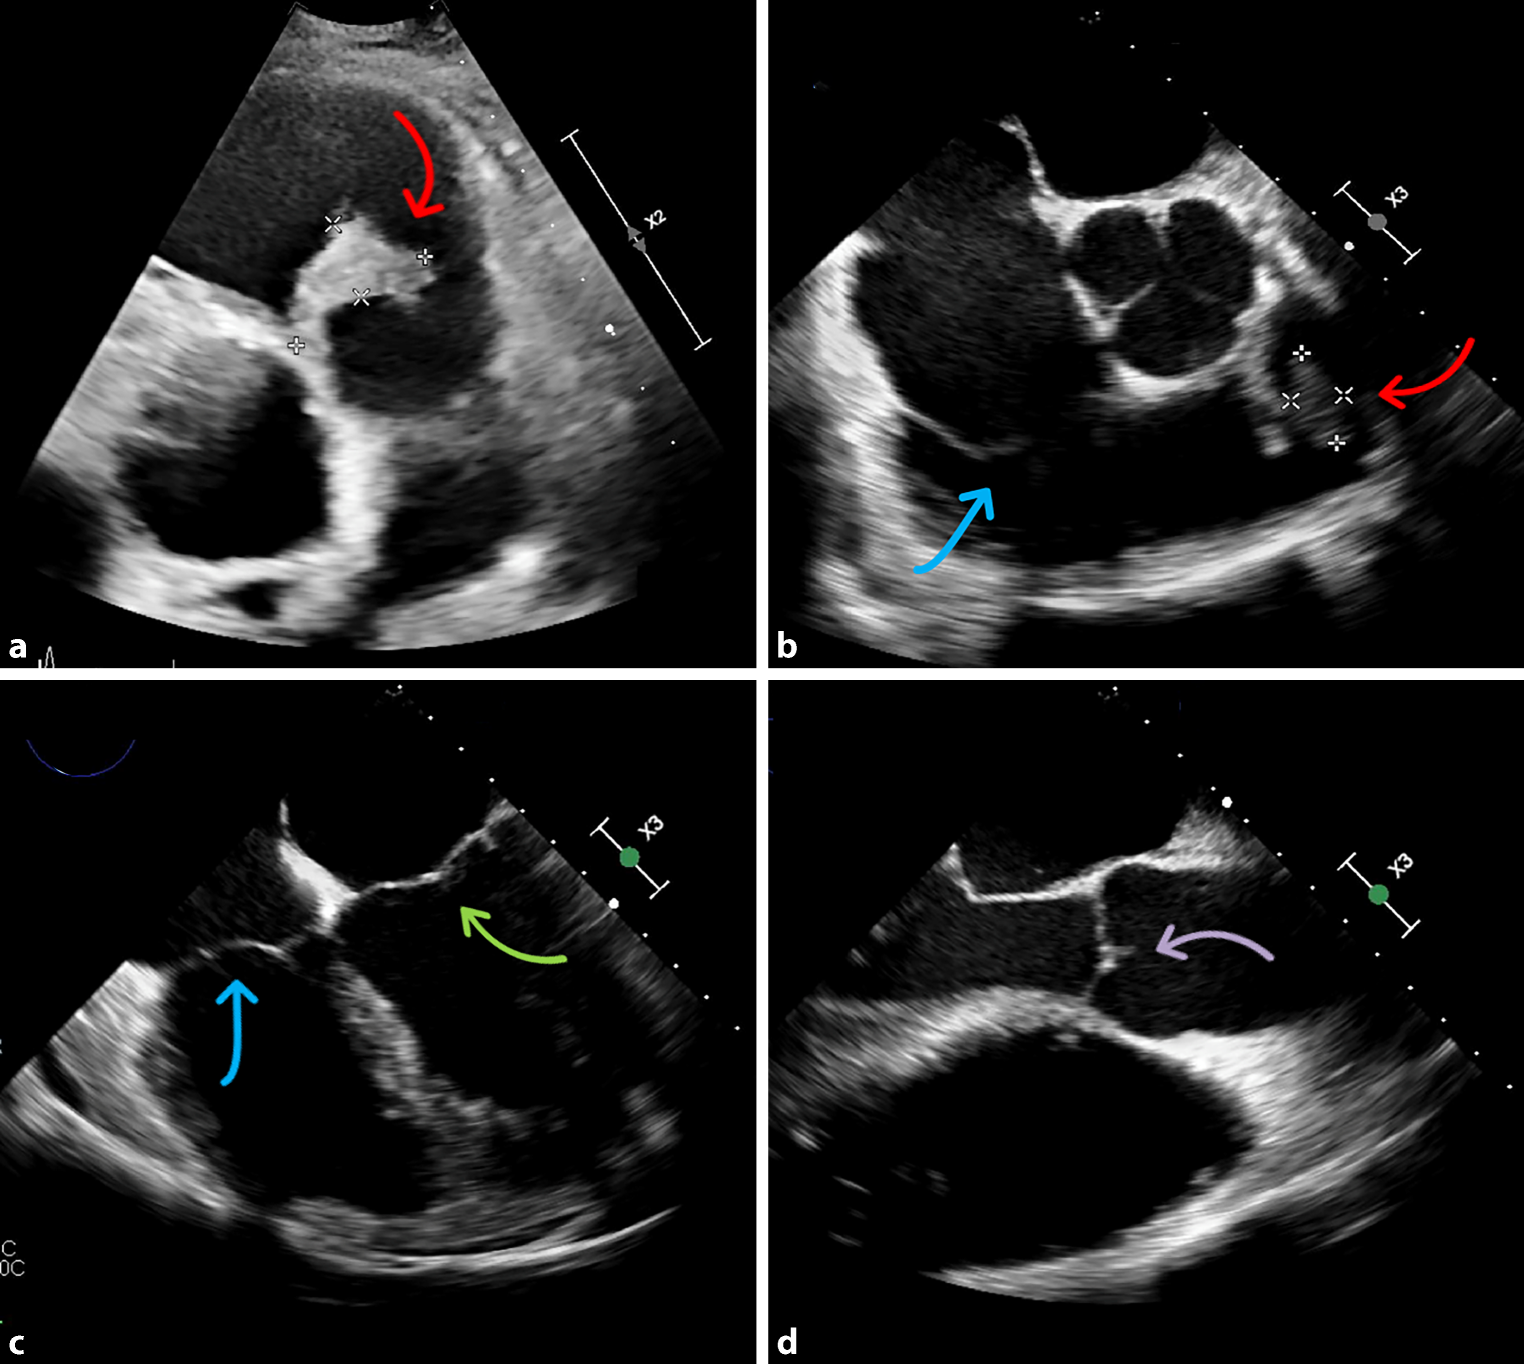

A 49-year-old male patient presented to the emergency department with fever and body aches. Laboratory tests showed increased infection and cholestasis parameters. Sonography revealed cholecystolithiasis, so the patient was admitted to the gastroenterology ward with suspected cholecystitis. An antibiotic regimen was established, but no improvement in the general condition of the patient could be achieved. Computed tomography of the thorax and abdomen revealed pericardial effusion and multiple peripheral pulmonary emboli. Thus, we performed transthoracic (TTE) and transesophageal echocardiography (TEE), where an isolated pulmonary valve endocarditis with a vegetation of 4 cm was detected (Fig. 1; Videos S1–S3). In the microbiological processing of the blood cultures, Streptococcus agalactiae, Staphylococcus haemolyticus and Staphylococcus pettenkoferi were detected. The patient was transferred to the cardiology ward and switched to antibiotic therapy with cefazolin and daptomycin in accordance with the antibiogram. Further diagnostic work-up revealed a carious tooth status and a necrotizing ulcer of the right second toe, most likely due to type 2 diabetes. One tooth was extracted and the ulcerated toe was amputated. Moreover, guideline-recommended antidiabetic therapy was initiated. In consultation with the Department of Cardiothoracic Surgery of our partner hospital, a conservative approach was primarily recommended; however, pulmonary valve replacement with a homograft was eventually performed due to persistently elevated infection parameters and the lack of improvement in echocardiographic findings. In fact, subsequent follow-up TEE, as demonstrated in the attached loops S1–S3, revealed progressive valve destruction with subsequent valve dysfunction.

Fig. 1

Vegetation at the pulmonary valve in transthoracic and transesophageal echocardiography. a Parasternal short axis view showing the vegetation on the pulmonary valve (red arrow). b Transesophageal echocardiography showing the vegetation at the pulmonary valve (red arrow) and the tricuspid valve (blue arrow) without any vegetation. c Transesophageal echocardiography showing the mitral valve (green arrow) and tricuspid valve (blue arrow) without any vegetation. d Transesophageal echocardiography showing the aortic valve without any vegetation (purple arrow)